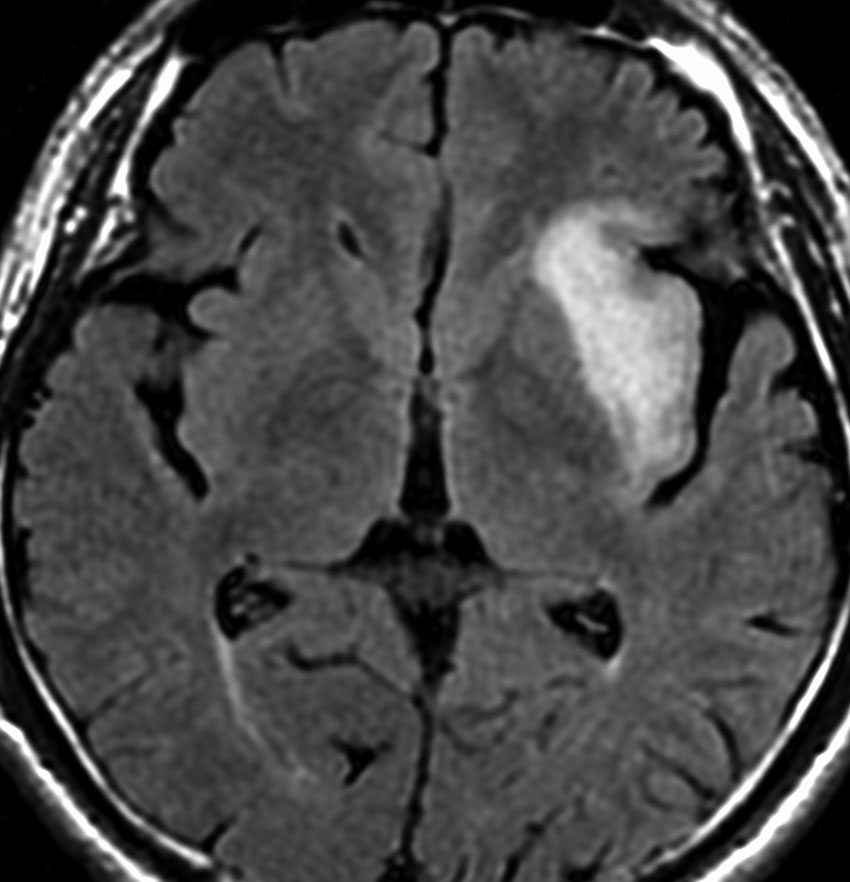

診断 MRI

• MRI-T1強調画像では低信号となり,T2強調画像とフレア画像では高信号域となります

• グリオーマの中では,T2強調画像での腫瘍内部のコントラストが強く,石灰化の部分は強い低信号域として,のう胞は均一な強い高信号域となります

• 周囲脳組織浮腫あるいは腫瘍浸潤部は淡い高信号域として描出されます

• 脳浮腫を伴うものはグレード3の可能性が高いです

• ガドリニウムによる造影では,悪性度が高くなるにつれて部分的な増強像が増えます

MRI画像ではびまん性星細胞腫と区別がつかないものがあります